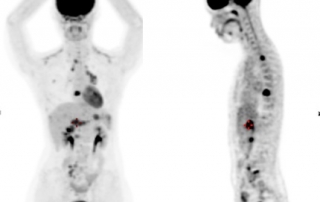

Examen clinique : adénopathie sus-claviculaire gauche, présence de sueurs nocturnes depuis un mois.

Hémogramme : hémoglobine 11.2 g/L, GB 7.9 G/L, lymphocytes 1.4 G/L, albumine 32 g/L, VS 98 mm.

Biopsie d’une adénopathie cervicale: lymphome de Hodgkin classique sclérose nodulaire riche en cellules tumorales.

Fibroscopie bronchique : compression extrinsèque de la lingula, biopsies bronchiques ne montrent pas d’infiltration tumorale.

Stade IV forme thoracique, atteinte médiastinale volumineuse et pulmonaire. Les examens d’imagerie ne montrent pas d’extension sous-diaphragmatique.

| Avant traitement | Après BEACOPP renforcé x 2 cycles Masse médiastinale dont le SUVmax est comparable au bruit de fond hépatique, correspondant à une réponse métabolique complète |

Résultat : la réponse métabolique complète après BEACOPP renforcé 2 cycles conduit à poursuivre le traitement par ABVD x 4 cycles selon l’essai AHL2011, avec évaluation après ABVD 2 cycles et en fin de traitement. La TEP-TDM montre une masse médiastinale résiduelle de taille 36 x 42 mm inchangée entre l’évaluation après 4 cycles et en fin de traitement, avec maintien de la réponse métabolique complète, correspondant à une diminution de 88%. Classement rémission complète incertaine selon les critères de Cheson 1999 et à une rémission complète selon les critères IWG 2007.